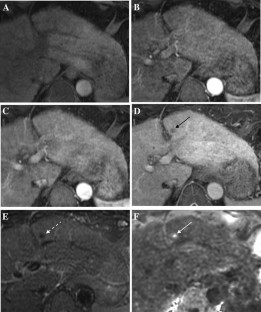

Fig. 2